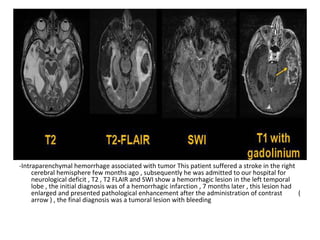

Differentiation between Infarct & Tumor

1-Clinical History

2-Distribution

3-Shape

4-Tissue Involvement

5-Advanced Imaging Techniques

1-Clinical History :

-Abrupt versus gradual onset and development of

symptoms

2-Distribution :

-Tumors not confined to vascular territory

3-Shape :

-Infarcts usually wedge shaped with base at

periphery , tumors tend to be spherical / ovoid

4-Tissue Involvement :

-Infarcts involve grey and white matter

-Most metastases or higher grade gliomas

involve white matter primarily

-Lower grade primary tumors may involve grey

matter

5-Advanced Imaging Techniques :

-Such as DWI or MR spectroscopy may be useful

in cases that remain unclear on standard

sequences